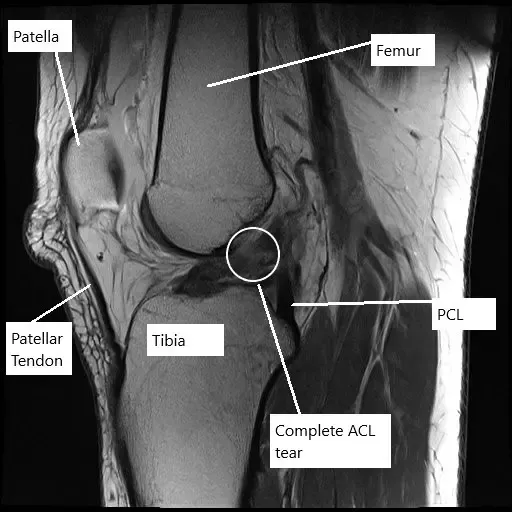

Resonancia magnética de la rodilla izquierda que muestra una rotura completa del LCA.

Un estudio radiológico en forma de resonancia magnética sugirió una rotura completa del LCA junto con desgarros complejos tanto del menisco medial como del lateral. La paciente deseaba ser atléticamente activa y continuar su trabajo sin episodios de inestabilidad.